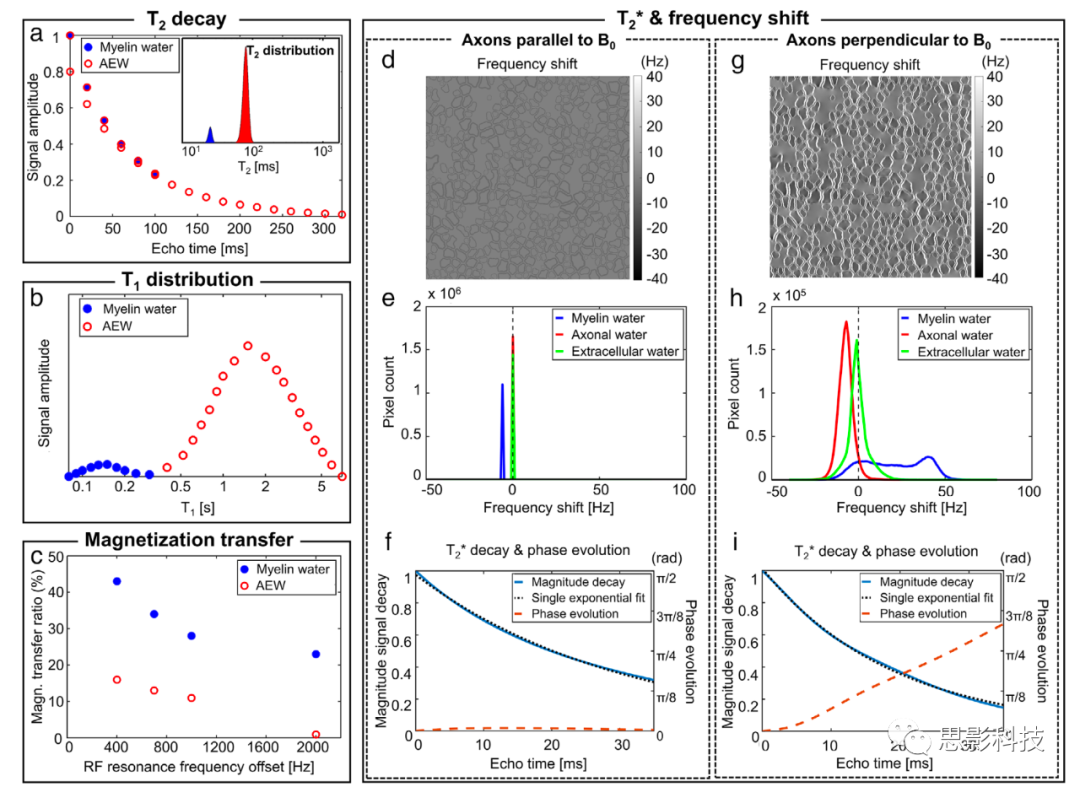

横向弛豫:与髓鞘的强烈相互作用使髓鞘水的T2在3T时缩短到大约20毫秒。5这个T2的范围可以在常规MWI序列中检测到,并且明显短于AEW信号。因此,当测量T2弛豫时,它显示为双(或多)指数衰减,如图2a所示。与T2相似,髓鞘水的T2*也比AEW的短。髓鞘水的较短T2*来源于髓鞘水的短T2和髓鞘的磁化率效应(图2d-i;参见下面的共振频率移位以获取更多细节)。

纵向弛豫:已报道髓鞘水的T1弛豫时间比AEW的短(图2b 23)。与T2相似,髓鞘水与周围脂质的相互作用引起交叉弛豫,导致髓鞘水的纵向弛豫时间减少。然而,实验中测得的T1值取决于采集参数(例如,反转脉冲类型和重复时间[TR]),这是由于反转效率和隔室水交换的效果。尽管存在这种复杂性,人们可以利用这一特性选择性地获取髓鞘水信号(参见基于T1的MWI)。

共振频率移位:这是髓鞘水信号与AEW信号不同的较少为人知的特性。关于髓鞘的磁化率的最近研究表明,髓鞘水的共振频率取决于白质纤维与B0之间的相对方向(图2d-i 15, 27)。当白质纤维垂直于B0时,髓鞘水频率移位显示出大的正频率移位,而轴突水产生相反的频率移位。这一独特特性的起源被归因于髓鞘水的磁化率各向异性。这种频率移位已被用于基于T2*的MWI以改进髓鞘水成像。

磁化转移:MT,起源于水分子池和大分子之间的磁化交换,是一个众所周知的现象。MT的效应大小(即,MT比率或MTR)受到大分子(例如,髓鞘)浓度的影响。已经证明髓鞘水信号的MT效应比AEW信号的高2-3倍(图2c 15, 16)。

图2:髓鞘水信号的特性。

(a) 白质中的一个典型T2信号衰减曲线。髓鞘水信号(蓝色实点)的T2比轴突/细胞外水(AEW;红色开放点)短,显示出更快的信号衰减。插图显示了一个具有两个明显峰值的T2分布,每个峰值分别对应于髓鞘水(蓝色)和AEW(红色)。

(b) 一个T1分布,表明髓鞘水的T1较短。

(c) 在不同的RF频率偏移下,髓鞘水和AEW之间的MTR比较。髓鞘水的MTR明显高于AEW的。

从(d-i),描绘了T2*和频率移位的特性。由于磁化率效应,三个隔室的T2*和频率移位取决于轴突和B0的相对方向。当轴突与B0平行时,只有髓鞘水获得一个小的负频率移位(e)。当轴突垂直于B0时,髓鞘水有一个广泛的频率移位分布(平均为大的正频率移位),而轴突水主要有相反的负频率移位(h)。这种频率移位导致非线性的相位演变(i;红色虚线)。